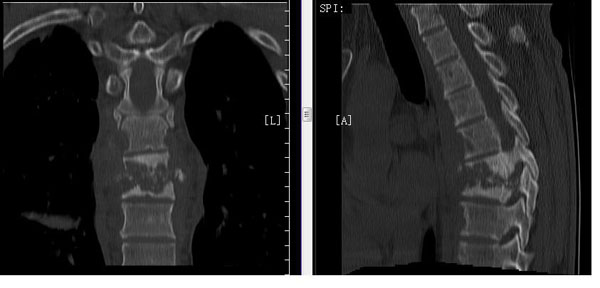

接诊后,许主任为樊先生进行了详细的检查,影像学检查提示脊柱结核破坏多个椎体,同时胸5-8椎体出现病理性骨折,椎旁脓肿,死骨形成,而樊先生既往有结核性胸膜炎,存在胸膜粘连,开胸入路时有胸膜破裂可能。许主任团队进行详细的术前检查评估及讨论,制定严谨的手术计划。术前抗结核治疗2周,复查血沉等正常后进行手术。手术虽然复杂,在手麻科的大力配合下,许主任手术团队沉着冷静,术中先俯卧位,微创(肌间隙)入路行胸5、6、9、10双侧椎弓根钉置入,连接棒固定,增强脊柱稳定性。后右侧卧位,改良小切口于病变节段开胸,截取相应节段肋骨备用,适当修剪肋骨条后,打压植入病灶,起到支撑融合作用。

手术顺利,术后1周,樊先生便可下床行走,胸背部疼痛明显缓解,无神经损伤症状,复查X片提示内固定位置好。术后2周恢复良好,拆线出院。术后1月,复查胸背部无明显不适,复查血沉均在正常范围,樊先生感叹道:“我都没想到我能恢复这么快!”12月6号,樊先生和家属特地送来两面锦旗,表达对脊柱外科许立新主任团队的感激之情。